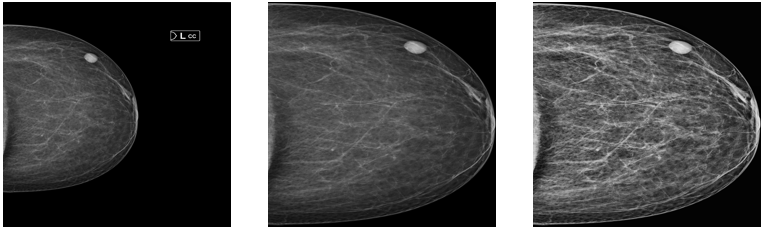

Mamografilerde kitle ve kalsifikasyon tespiti ile BI-RADS sınıflandırma

Bu projede, meme kanserinin erken dönem teşhisine yönelik bir karar destek sistemi geliştirilmiştir. Çözüm, hekimlerce kullanılan BI-RADS risk sınıflandırmasını ve şüpheli kitle ile kalsifikasyon tespitini kapsamaktadır; her iki görevde de %90’ın üzerinde başarı elde edilmektedir.

Tespit görevlerinde YOLO ile ABC tabanlı hiperparametre optimizasyonu kullanılmıştır. Sınıflandırma görevlerinde ise negatif tabanlı kolektif öğrenme yaklaşımı EfficientNet-B1 üzerinde uygulanmıştır. Bu yaklaşımın, literatürde standart sınıflandırma düzeneklerine kıyasla üstün performans gösterdiği gözlemlenmiş olup, bulgular makale olarak hazırlanmaktadır.